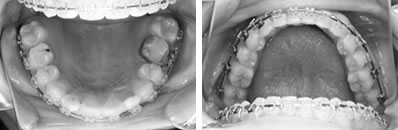

前歯の反対咬合と凸凹を解消した8歳

前歯の反対咬合と、それに合せて歯肉が下がっていることが心配されました。下顎の凸凹も問題でした。

上顎左側の2番目の永久歯(側切歯)が反対咬合です。まだ乳歯も多く残る歯並びですが、全体に凸凹が認められます。